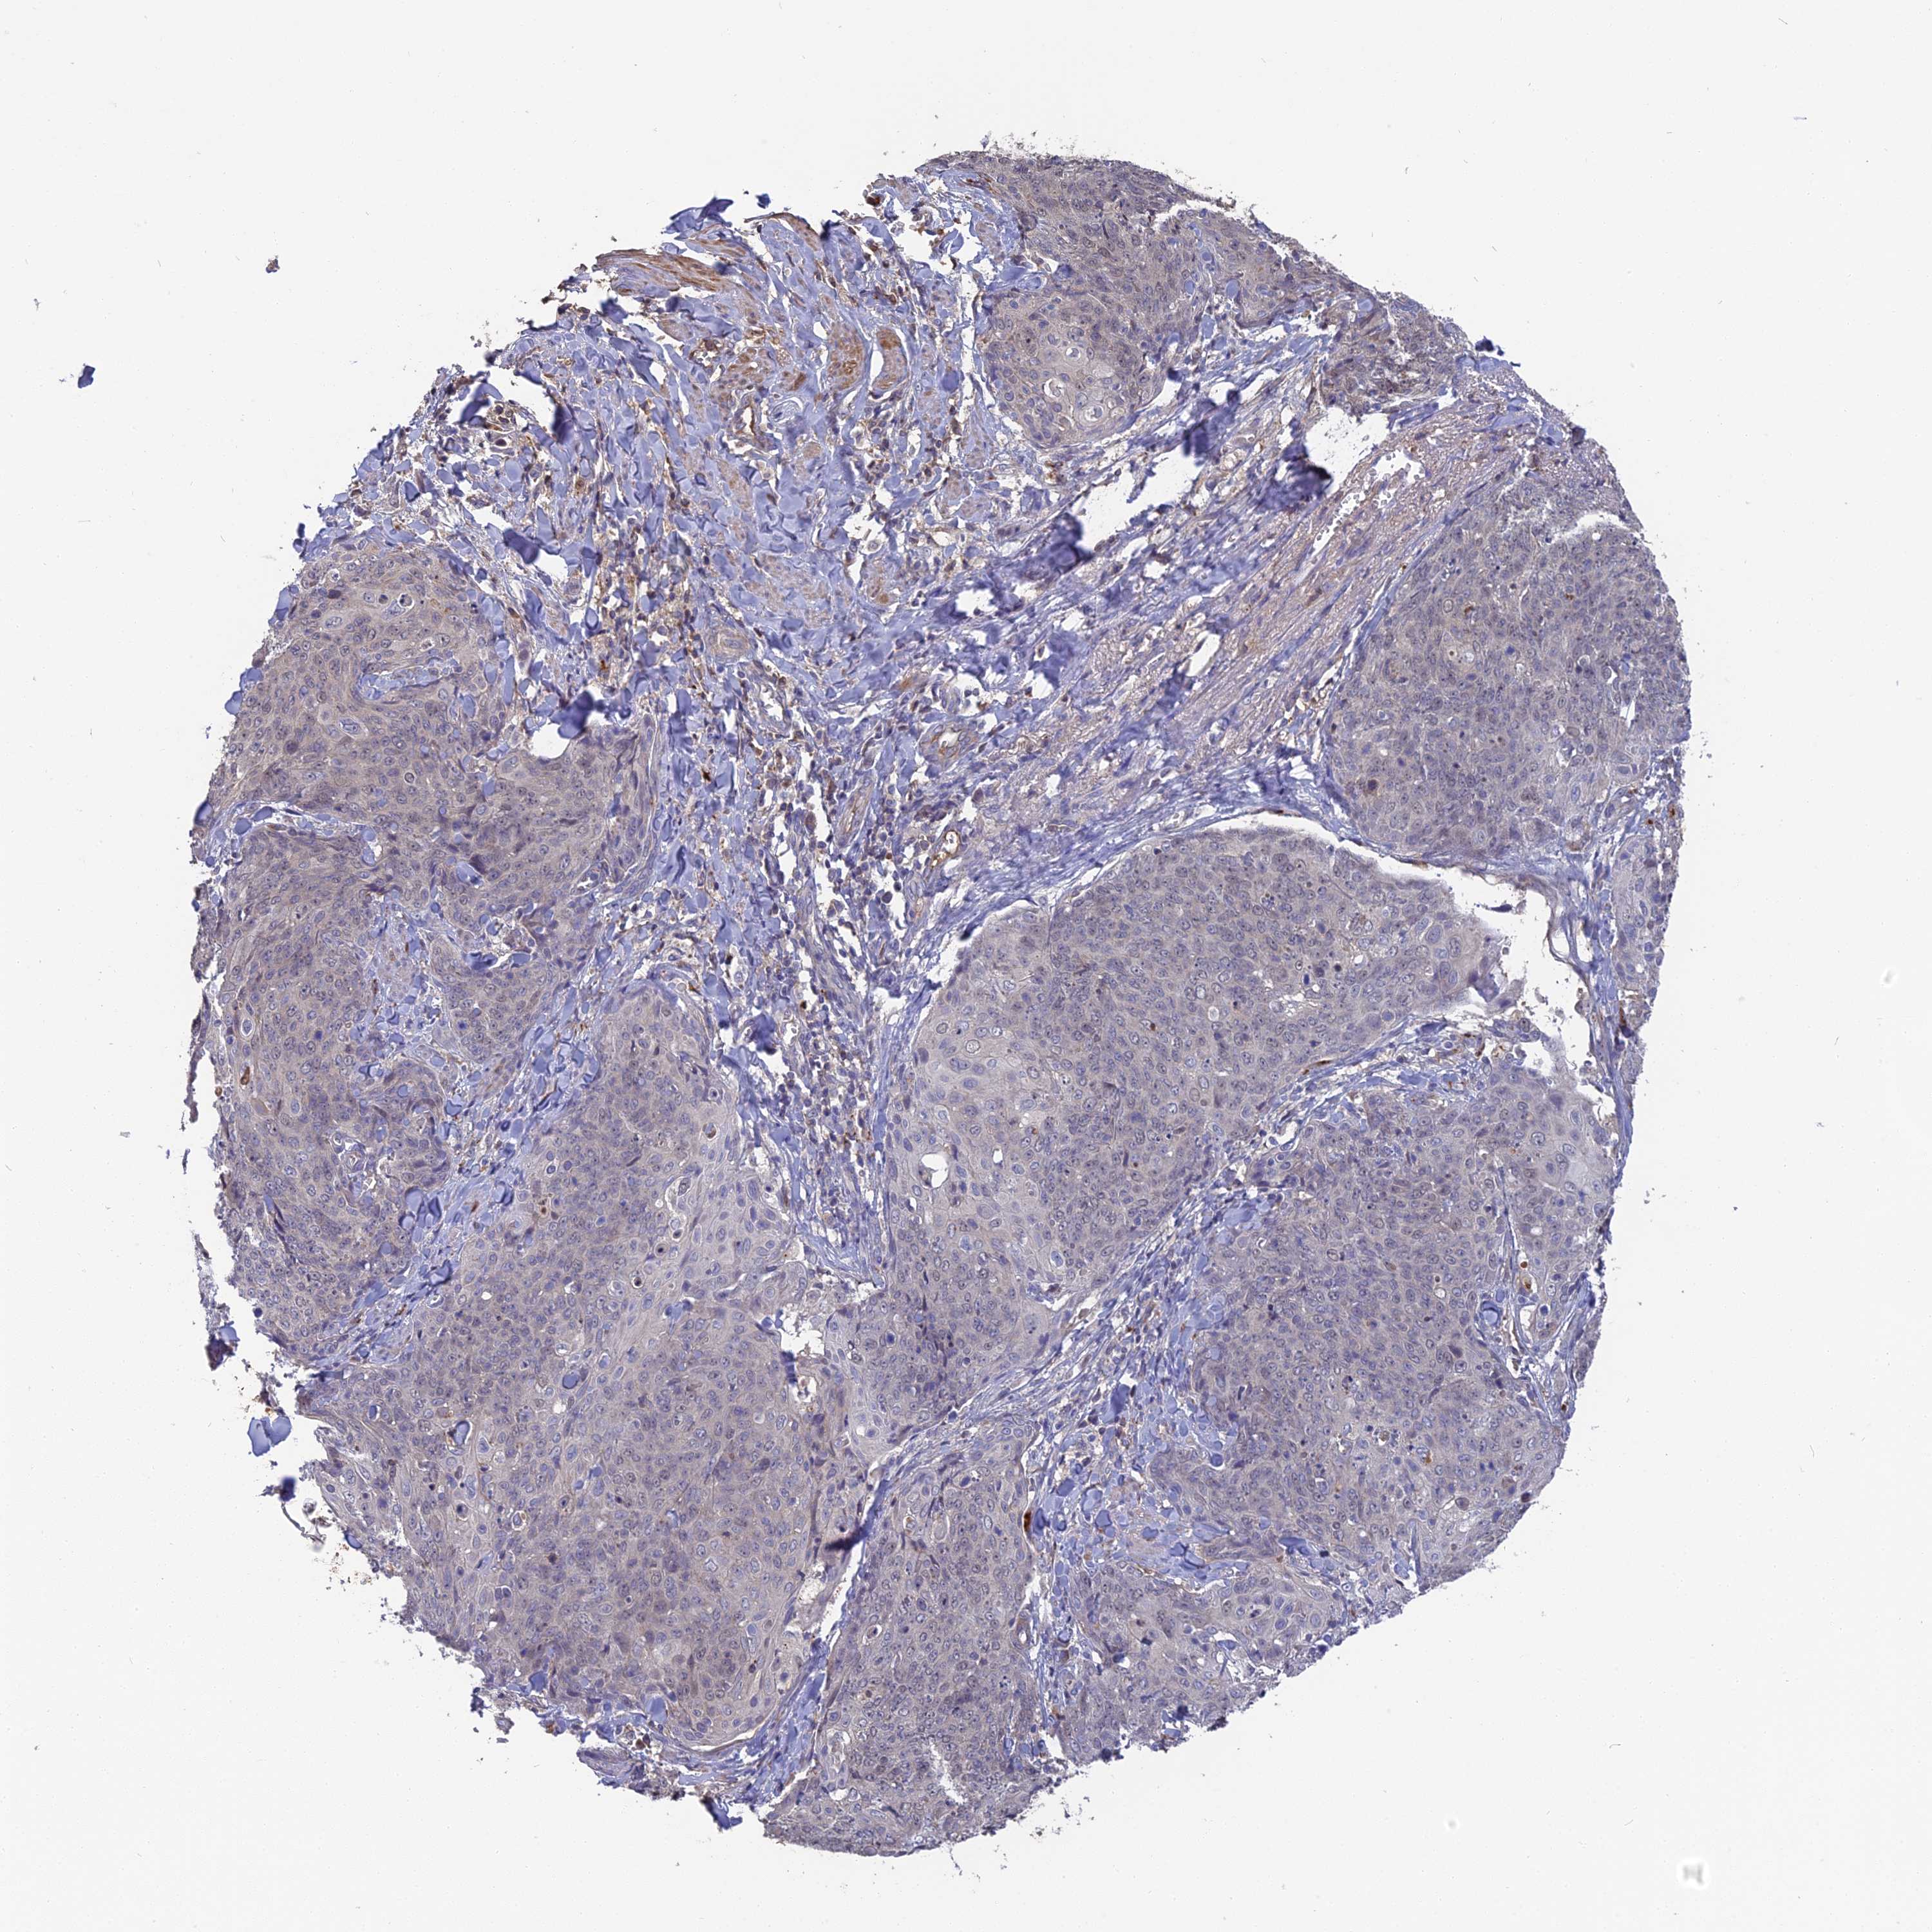

SKIN CANCER - Protein expressioni

A mouse-over function shows sample information and annotation data. Click on an image to view it in a full screen mode. Samples can be filtered based on level of antibody staining by selecting one or several of the following categories: high, medium, low and not detected. The assay and annotation is described here.

Each image is clickable and will lead to virtual microscopy that enables deeper exploration of all samples and also displays staining intensity scores, fraction scores and subcellular localization as well as patient and tissue information for each sample.

Antibody HPA042573

Squamous cell carcinoma, NOS